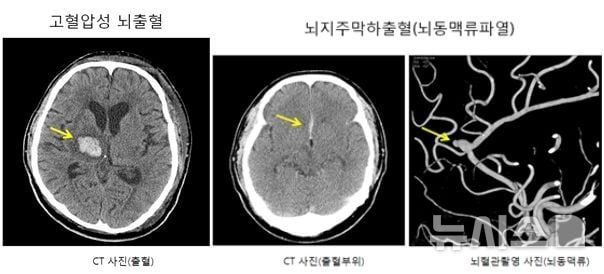

의료계에 따르면 뇌출혈은 매년 약 2만4000명이 발병하며, 국내 사망원인 4위에 해당하는 심각한 질환이다. 뇌동맥류와 고혈압이 대표적인 원인으로 꼽히는데, 뇌동맥류의 경우 정상 혈관 일부가 비정상적으로 팽창해 출혈을 초래한다. 국내에서는 연간 약 6만건의 비파열성 뇌동맥류가 조기 발견되지만, 약 6500건은 실제 파열 후 진단된다. 고혈압성 뇌출혈은 구조적 뇌혈관질환이 없더라도 모세혈관이 압력에 못 견뎌 터지면서 발생하며, 다른 기저 뇌혈관 질환에 의한 출혈도 원인이 된다. 두부 외상에 의한 외상성 뇌출혈도 주요한 한 형태다.

특히 뇌출혈은 전조증상이 거의 없어 진단의 시기가 늦어질 수 있다. 통상적으로 극심한 두통과 함께 한쪽 팔다리 마비, 의식 흐림 등의 증상이 동시에 발현될 경우 신속한 병원 내원 및 진단이 필수적이다. 출혈 직후부터 손상이 빠르게 진행되며, 뇌부종이나 재출혈이 이어질 위험이 높아진다. 환자에게는 빠른 치료 결정이 중요하다. 치료의 축은 응급 수술이나 약물로 뇌압 상승을 억제함과 동시에, 재출혈 방지를 위한 근본 원인 치료에 맞춰진다.